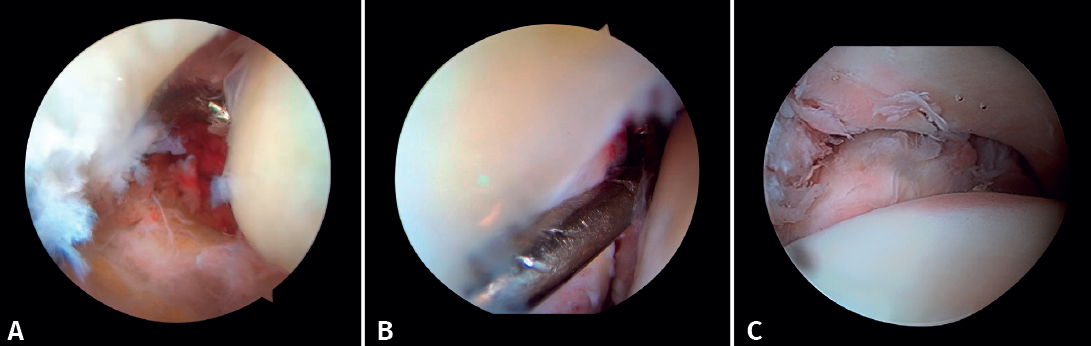

If possible, we reinsert unstable osteochondral fragments (Figure 3). In chondral lesions where it is not possible to reinsert the fragment, cartilage repair stimulation techniques can be used(5,13).

Arthroscopy assists ORIF in evaluating the congruence of the joint surface. It is especially useful for reduction of the medial malleolus. The malreduction rate in medial malleolus fractures is 22.2-32.6%(15,16). Initial arthroscopy allows us to determine whether tibial malleolus reduction can be performed in an open or closed manner. In cases with significant displacement, open synthesis is chosen, always maintaining arthroscopic control during the procedure to ensure precise reduction and avoid rotation of the distal fragment (Figure 4).

If the deltoid ligament injury involves only the anterior part, arthroscopic reinsertion can be made using resorbable implants. If deltoid ligament disinsertion is complete, open reinsertion is preferred, because of the difficulty of placing the implants in the posterior malleolus and the risk of neurovascular injury (Figure 5).